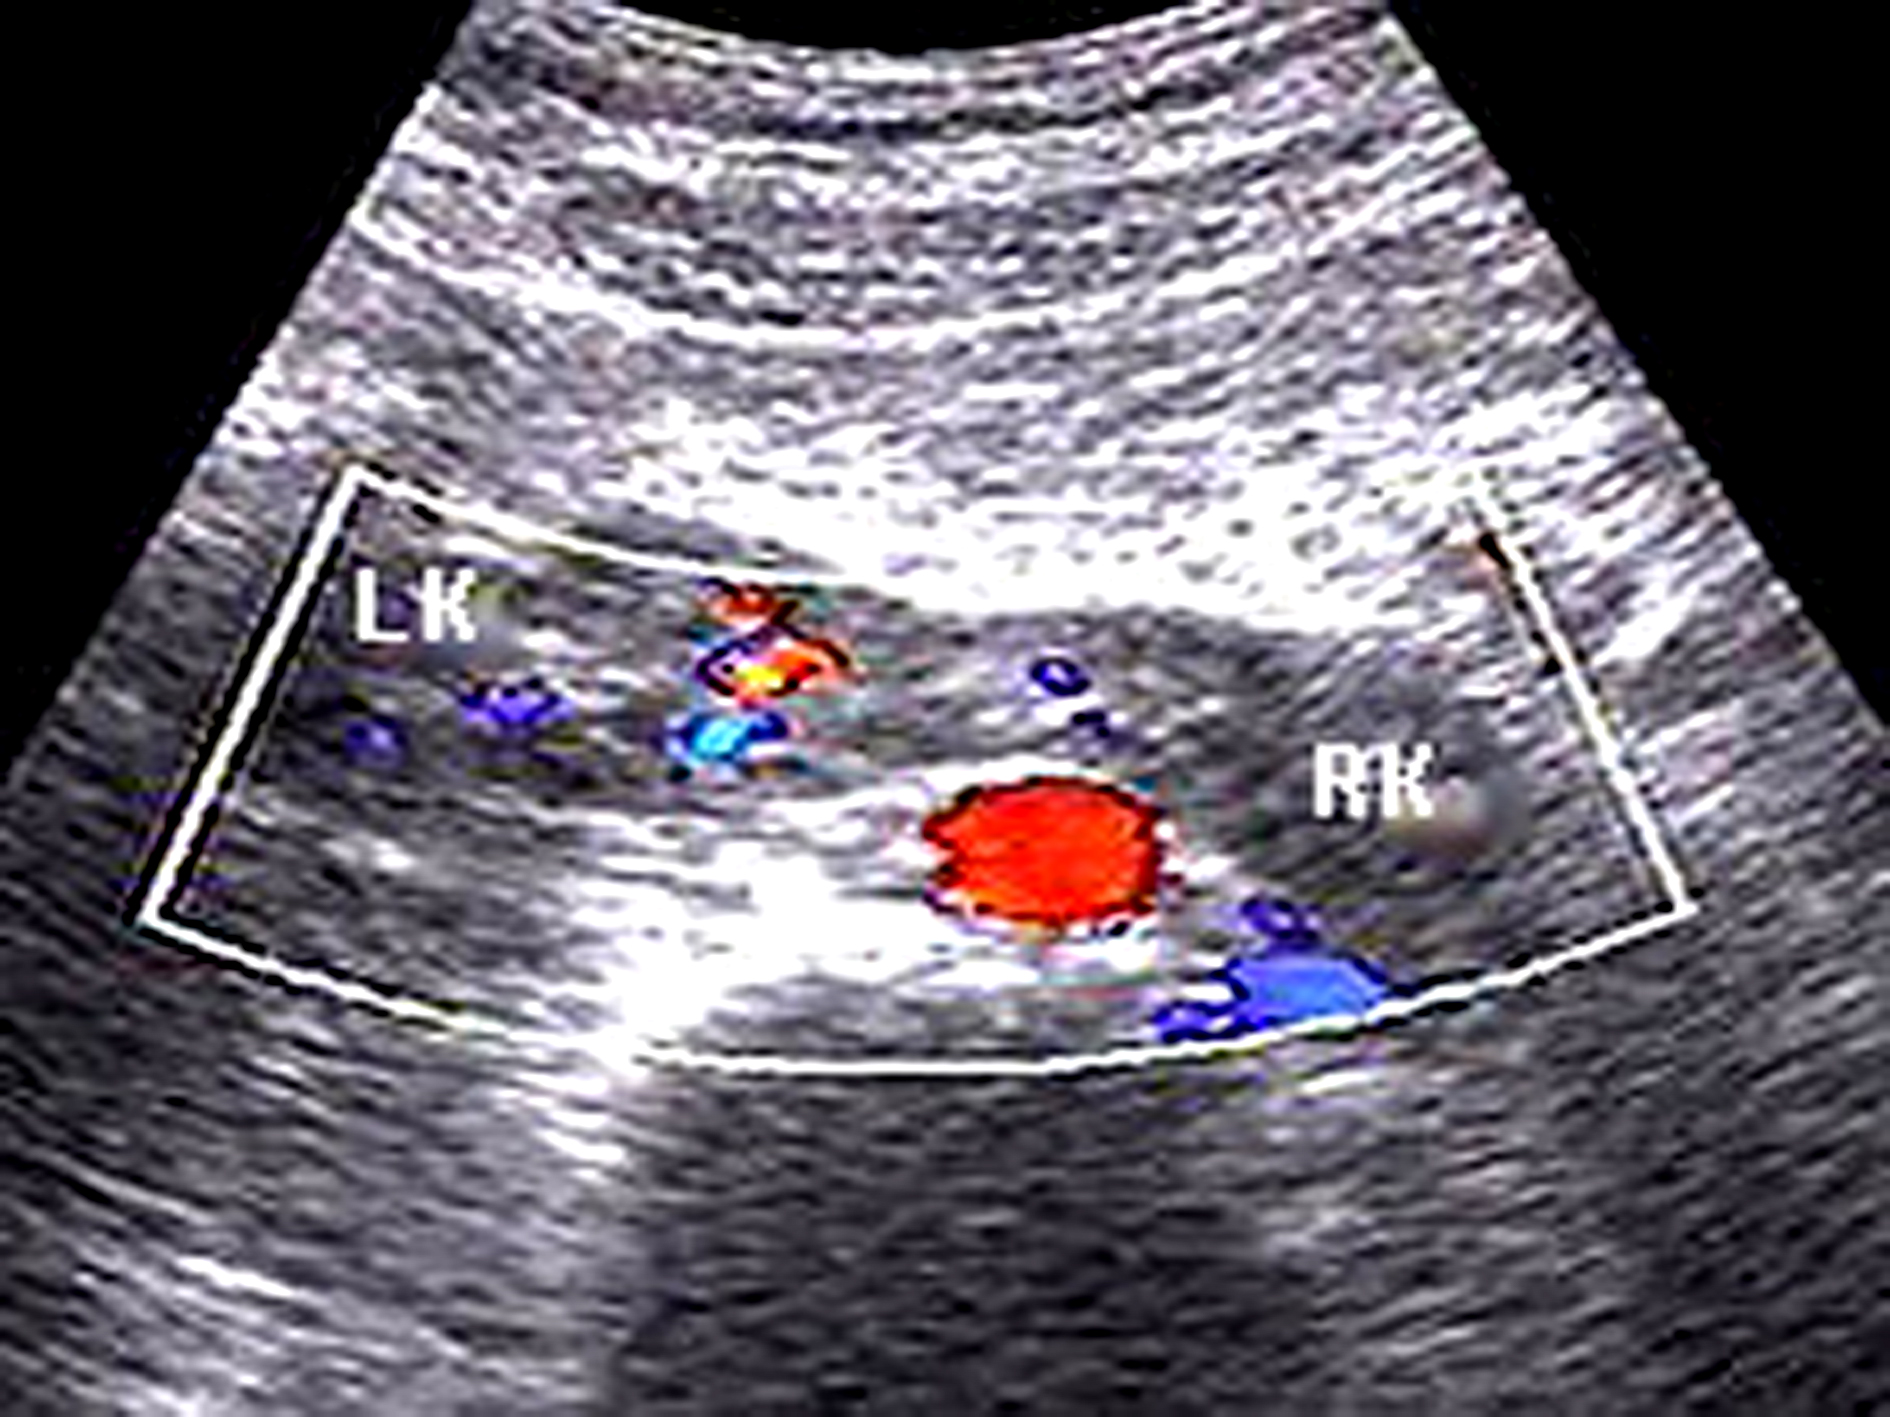

单侧肾缺如又称孤立肾。由于有对侧发育正常的肾脏而不出现羊水过少,胎儿膀胱亦可显示良好,发育正常的肾脏呈代偿性增大。肾脏缺如的一侧超声不能显示肾脏图像,但可显示肾上腺“平卧”征,彩色多普勒可显示该侧肾动脉缺如,而健侧肾动脉存在(图1)。诊断单侧肾缺如时,应特别仔细检查腹内尤其是盆腔内有无异位肾存在,在除外异位肾的情况下才能诊断单侧肾缺如。

图1 孕28周,胎儿一侧肾缺如,肾动脉血流未显示